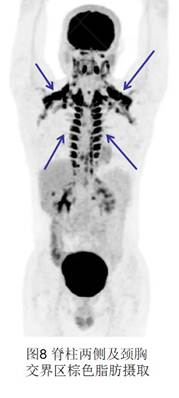

8、棕色脂肪。精神緊張及寒冷刺激可出現(xiàn)棕色脂肪生理性攝取,最常見于雙側(cè)頸部、鎖骨區(qū),其次為腋窩、縱隔、肋間、脊柱旁和腎周區(qū)域(圖8),多見于兒童、年輕女性、寒冷季節(jié)。所以在PET檢查過程中要適度保暖,避免出現(xiàn)棕色脂肪的高攝取。